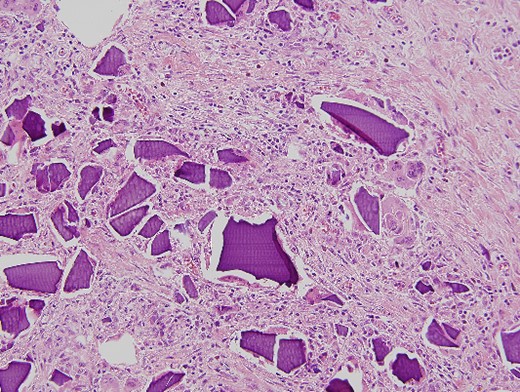

An urgent laparotomy exposing the terminal ileum was performed, signs of intestinal suffering were evident in relation with a thickening and a retraction of the mesoileum at the terminal ileum responsible for the small bowl obstruction. An ileocecal resection with immediate side-to-side ileocolic anastomosis was performed (Fig. 3). Microscopic pathological examination: abundant calcium polystyrene sulfonate crystals along the intestinal wall surrounded by intense inflammatory infiltrate (Figs 4 and 5).

Macroscopic pathological examination: mesenteric hypertrophy surrounding the mesoileum causing stricture of the intestinal lumen.

Microscopic pathological examination: abundant calcium polystyrene sulfonate crystals along the intestinal wall surrounded by intense inflammatory infiltrate.